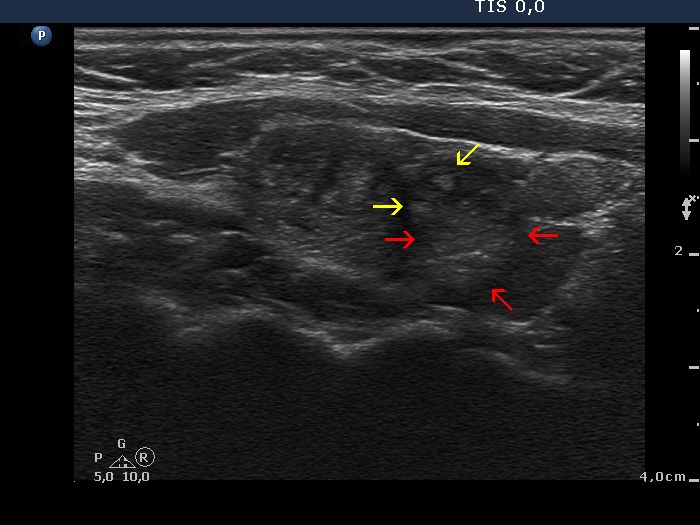

Discrete lesion or nodule in Hashimoto's thyroiditis - case 20 (698) (ultrasonographic picture 2b)

ight lobe, longitudinal view. The red arrows point to minimally hypoechogenic part while the yellow do to the ragged echonormal fragments.